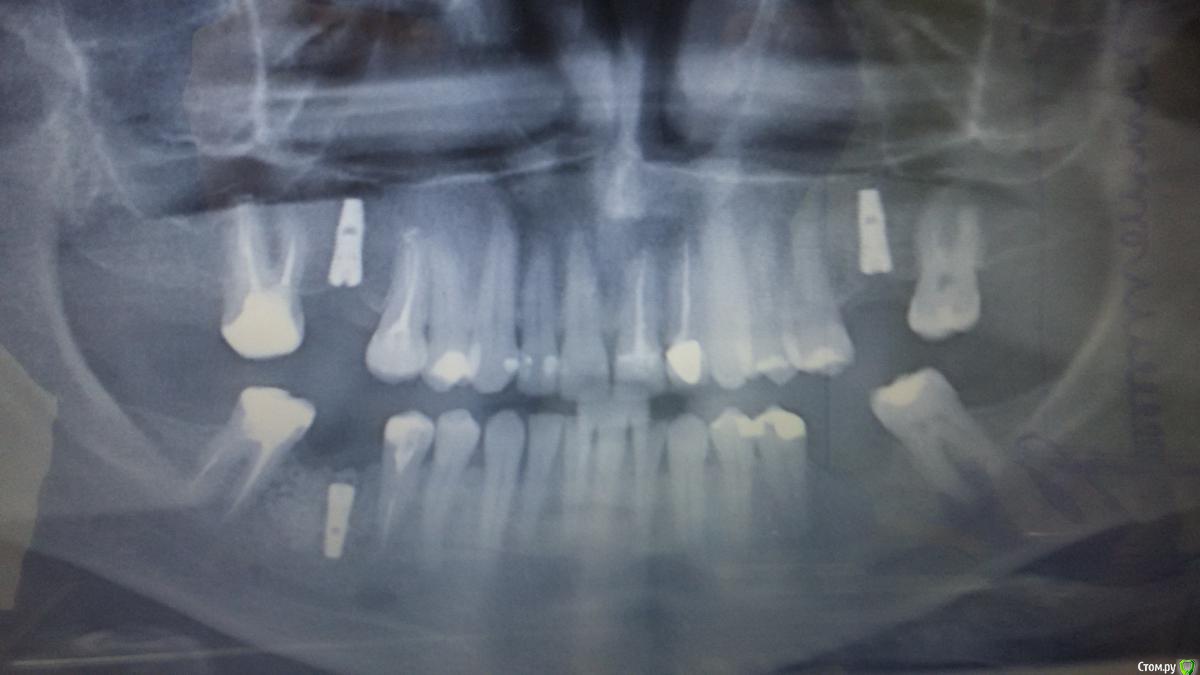

kipish Опубликовано 12 декабря, 2015 Поделиться Опубликовано 12 декабря, 2015 Снимок прилагаю.Интересует верхняя "шестерка" слева.Имплант установленный на этом месте случайно не попадает в гайморову пазуху?По сравнению с верхним имплантом установленным на месте "шестерки" справа видно что есть еще запас кости под имплантом в направлении пазух. А под верхним имплантом слева - вроде как нет.В дальнейшем - после установки коронки на имплант - он не провалится под нагрузкой в пазуху? Ссылка на комментарий

Evikrol Опубликовано 12 декабря, 2015 Поделиться Опубликовано 12 декабря, 2015 Гайморова пазуха у вас начинается в области седьмых зубов. Имплантат никуда не провалится. До гайморовой очень далеко 1 Ссылка на комментарий